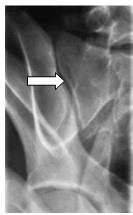

Którą strukturę anatomiczną zaznaczono strzałką na rentgenogramie?

A. Staw krzyżowo-biodrowy.

B. Kość kulszową.

C. Kość krzyżową.

D. Talerz biodrowy.